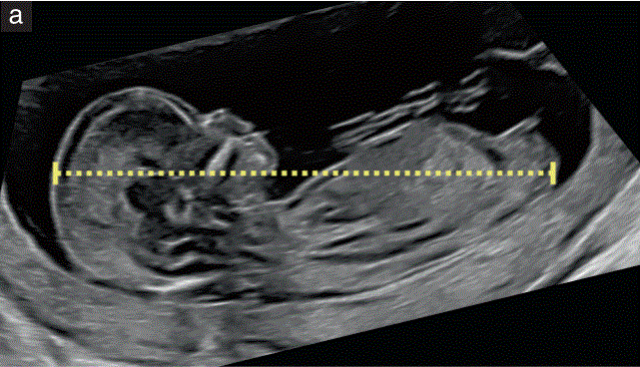

•  头臀长度(CRL)应作为常规孕早期检查的一部分进行测量,无论是经腹还是经阴道(图1-a)。

• 这种测量应该 应按照标准切面进行。

--胎儿在屏幕上的方向是水平的, 胎头和胎臀之间的测量线与超声束的约为成90度角。

--胎儿应处于自然状态(即既不弯曲也不过度伸展)。

--图像应该充分放大,充满超声屏幕的大部分宽度;

--卡尺应放在头冠和臀部的端点,需要清晰地观察;

• CRL的测量应用于估计所有情况下的胎龄,体外受精妊娠除外;

• 当进行多次CRL测量时,应根据45至84 mm之间的最佳CRL测量值评估胎龄;

• 已经发表了许多不同的图表,报告的胎龄测量值存在微小但显著的差异;虽然旧的图表仍被广泛使用,但建议使用最近的国际规范性图表,因为这些图表 考虑到图像和机器质量的改进,旨在避免可能的统计偏差;

• CRL(而不是计算的胎龄)应作为妊娠参考,以确定NT、UtA多普勒脉动指数(PI)和无生化标志物β-人绒毛膜促性腺激素(β-hCG)、妊娠相关血浆蛋白-a(PAPP-a)和胎盘生长因子(PlGF)的测量值与正常范围的关系;

• 受18三体和三倍体影响的胎儿CRL降低,在有明显结构异常的胎儿中,应注意不要通过改变日期来 "正常化 "研究结果。如果CRL小于早期超声测量的预期值,则应特别注意。

图1 11+0至14+0周胎儿超声检查可获得的测量值。(a)用于评估胎龄 测量胎儿的头臀长度(CRL),以评估胎龄。在测量CRL时,卡尺的位置应对应于从胎儿头顶到臀部的最长直线。